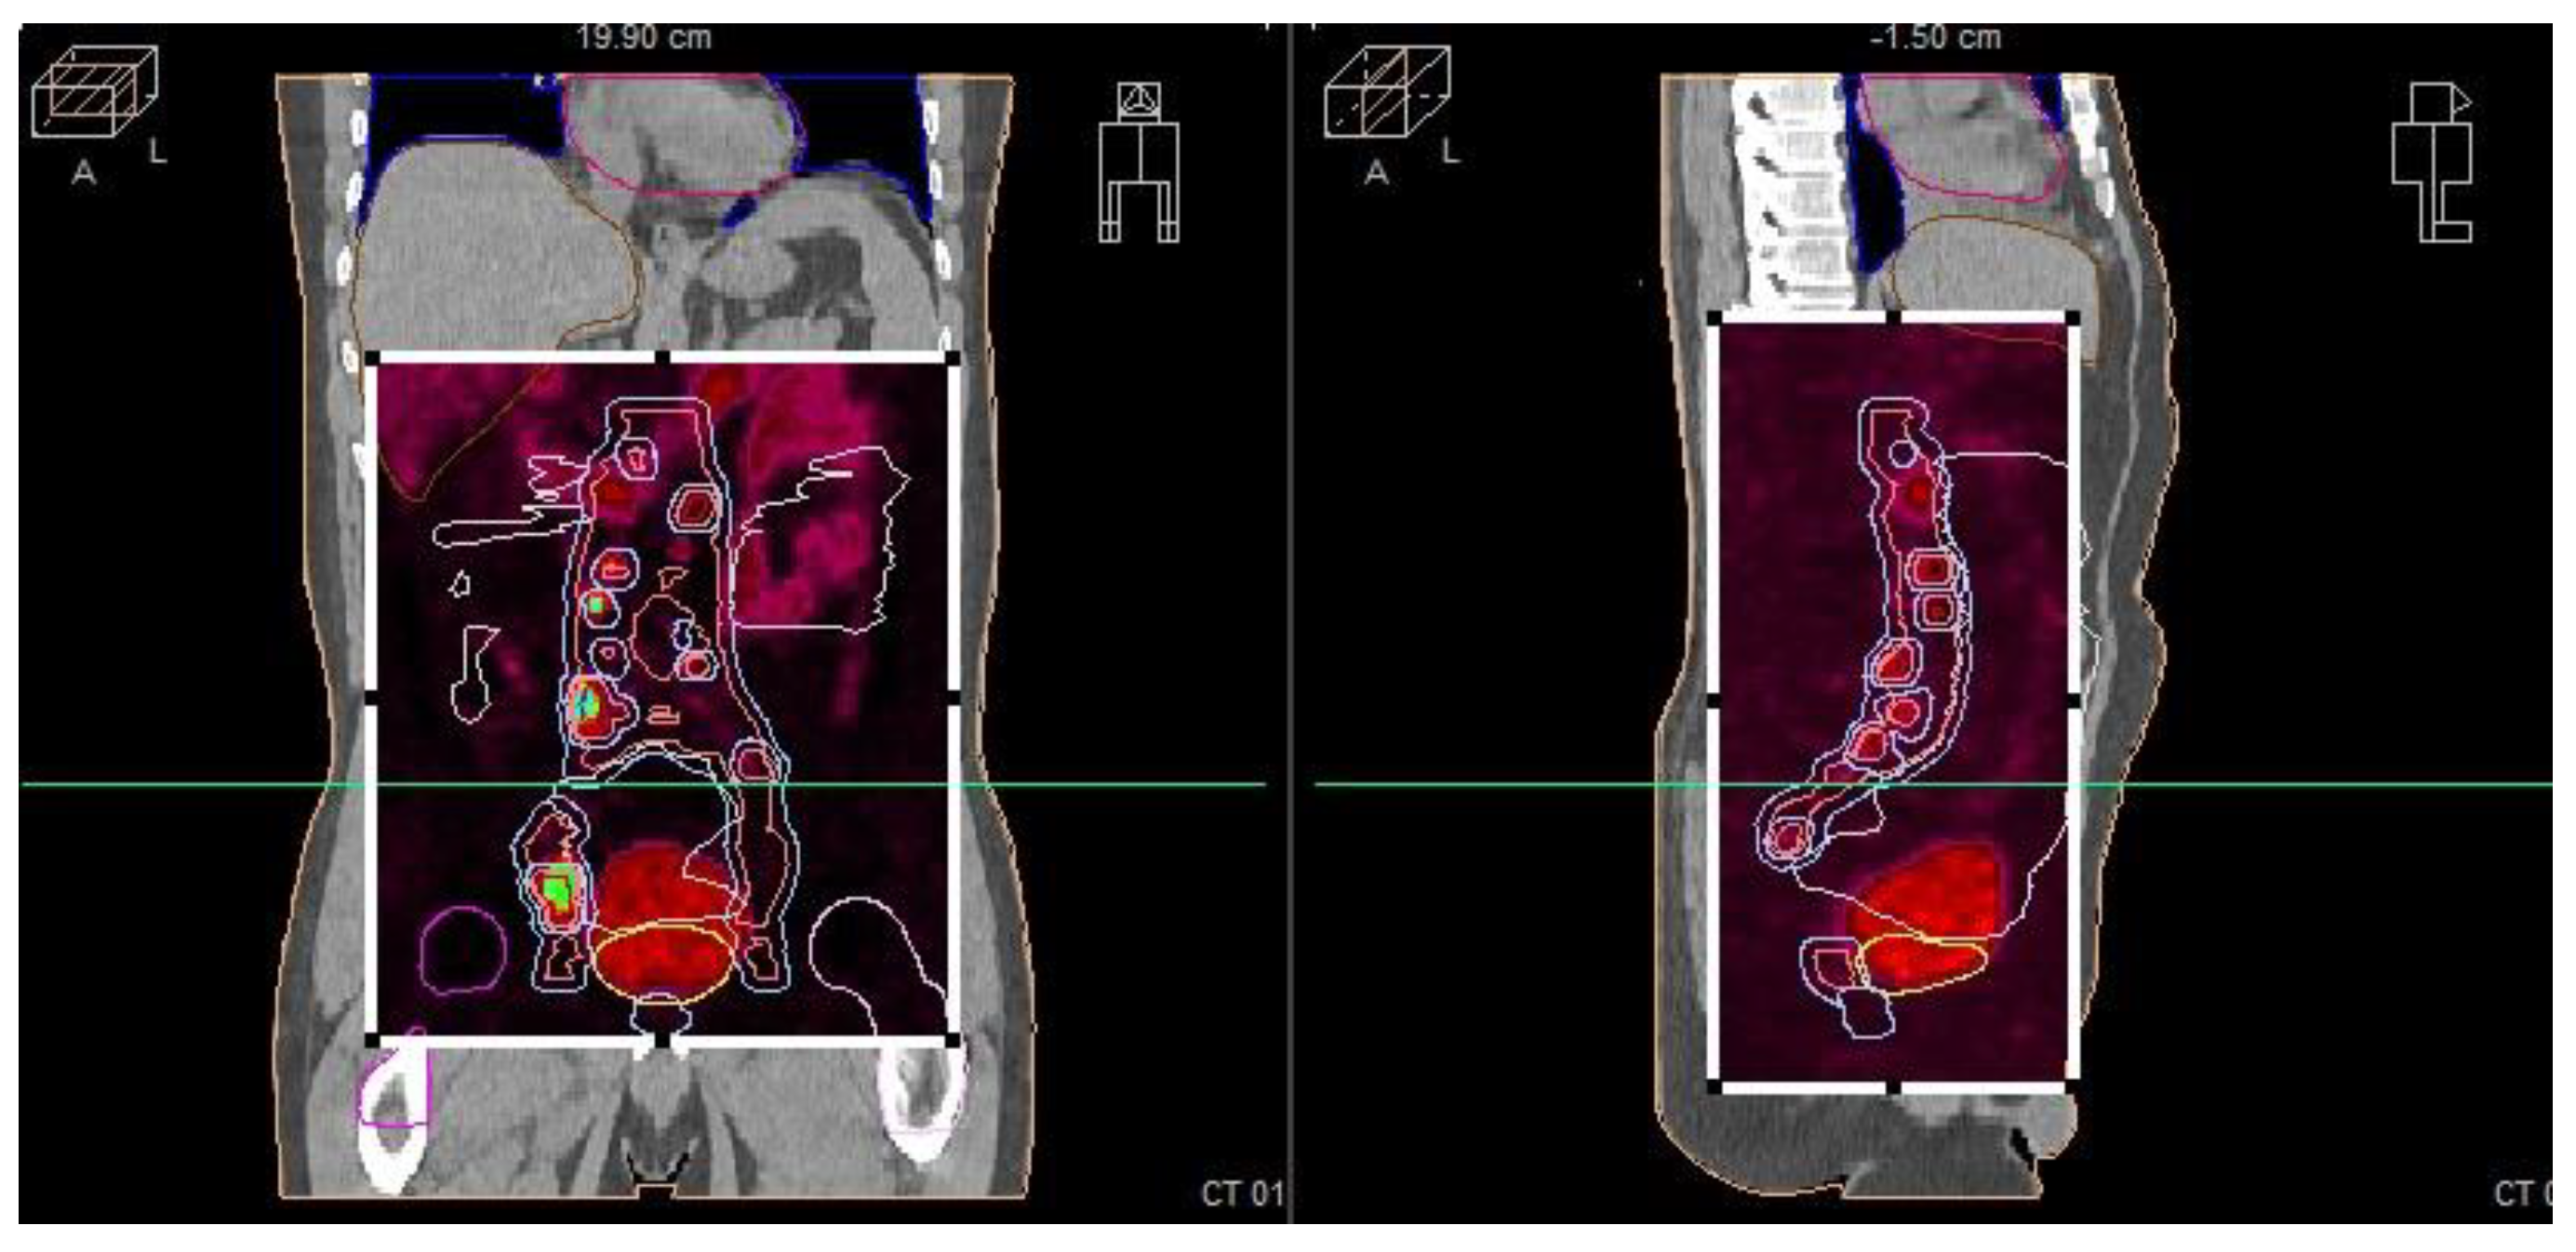

To better understand the distribution and activity of the cancer, a PET/PSMA scan was conducted. This imaging modality provided detailed information on the metastatic spread and the primary tumor’s metabolic activity. Following these diagnostic procedures, the patient was treated with androgen deprivation therapy using leuprorelin.

The patient’s initial PSA level was 280 ng/mL at diagnosis, and a prostate biopsy confirmed adenocarcinoma with a Gleason score of 7 (4 + 3), WHO Grade group 3. CT imaging of the abdomen and pelvis revealed extensive metastasis to the pelvic lymph nodes, including the obturator, external iliac, and common iliac nodes, as well as involvement in the para-aortic space. A bone scintigraphy showed no signs of bone metastasis. Subsequent PET/PSMA imaging (Figure 4) identified pathological tracer uptake in the majority of the prostate tissue bilaterally, with an SUV max of 19.2 and a visual score of 3, E-PSMA 5. Numerous pelvic lymph nodes, including the external, internal, and common iliac nodes bilaterally, showed an SUV max of 36.2 and a short-axis diameter up to 22 mm, visual score 3, E-PSMA 5. Additionally, retroperitoneal lymph nodes on both sides showed SUV max values up to 32 and short-axis diameters up to 9 mm, visual score 3, E-PSMA 5. The distribution of the radiotracer was otherwise physiological.

Based on these findings, the patient was classified as having stage cT2N1M1a prostate cancer with metabolically active disease in the prostate and extensive lymph node involvement. After receiving six cycles of docetaxel chemotherapy, his PSA level decreased from 118 ng/mL to 6.81 ng/mL. However, subsequent CT imaging of the abdomen and pelvis continued to show extensive lymph node metastases.

Figure 4. PET/PSMA scan of the patient showing metastatic sites in the prostate and lymph nodes. The scan highlights the primary tumor site in the prostate and identifies metastatic lymph nodes, illustrating the spread of the disease.